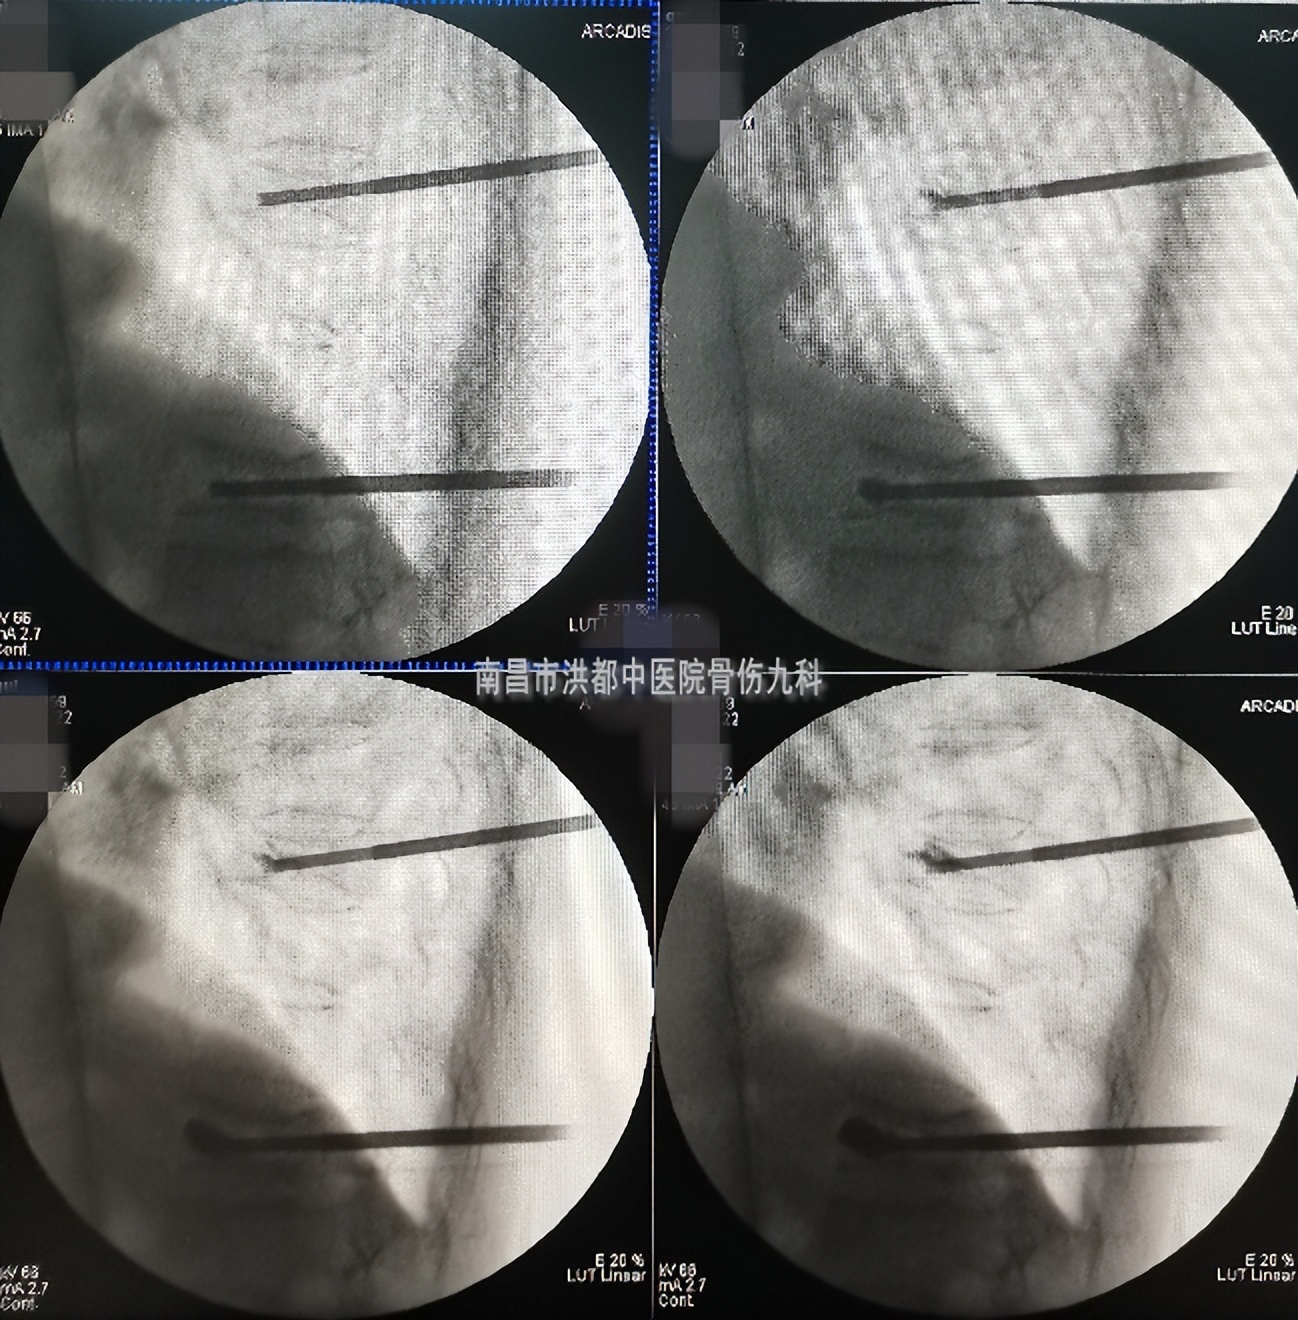

因诊断明确,具备手术指征,在排除手术禁忌症后,副主任医师刘晓平顺利为钱婆婆行椎体骨折后路经皮穿刺椎体成形术,仅30余分钟,通过两个小切口,利用特制的穿刺针,在X射线监护下将“骨水泥”注入压缩骨折的部位,以稳定受损的椎体,这样不仅可以防止进一步塌陷,还可以明显缓解局部疼痛。

术中影像